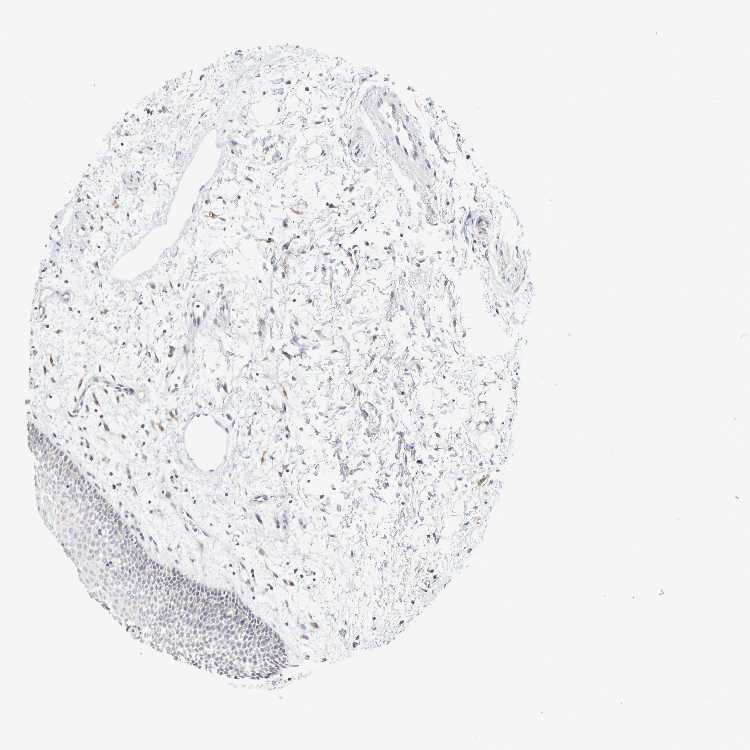

TISSUE PRIMARY DATA ORAL MUCOSA Show tissue menu

ORAL MUCOSA - Antibody stainingi

Antibody staining in the annotated cell types in the current human tissue is reported as not detected, low, medium, or high, based on conventional immunohistochemistry profiling in selected tissues. This score is based on the combination of the staining intensity and fraction of stained cells.

Each image is clickable and will lead to virtual microscopy that enables deeper exploration of all samples and also displays staining intensity scores, fraction scores and subcellular localization as well as patient and tissue information for each sample.

Antibody HPA021125Antibody HPA023086

Squamous epithelial cells Not detectedNot detected